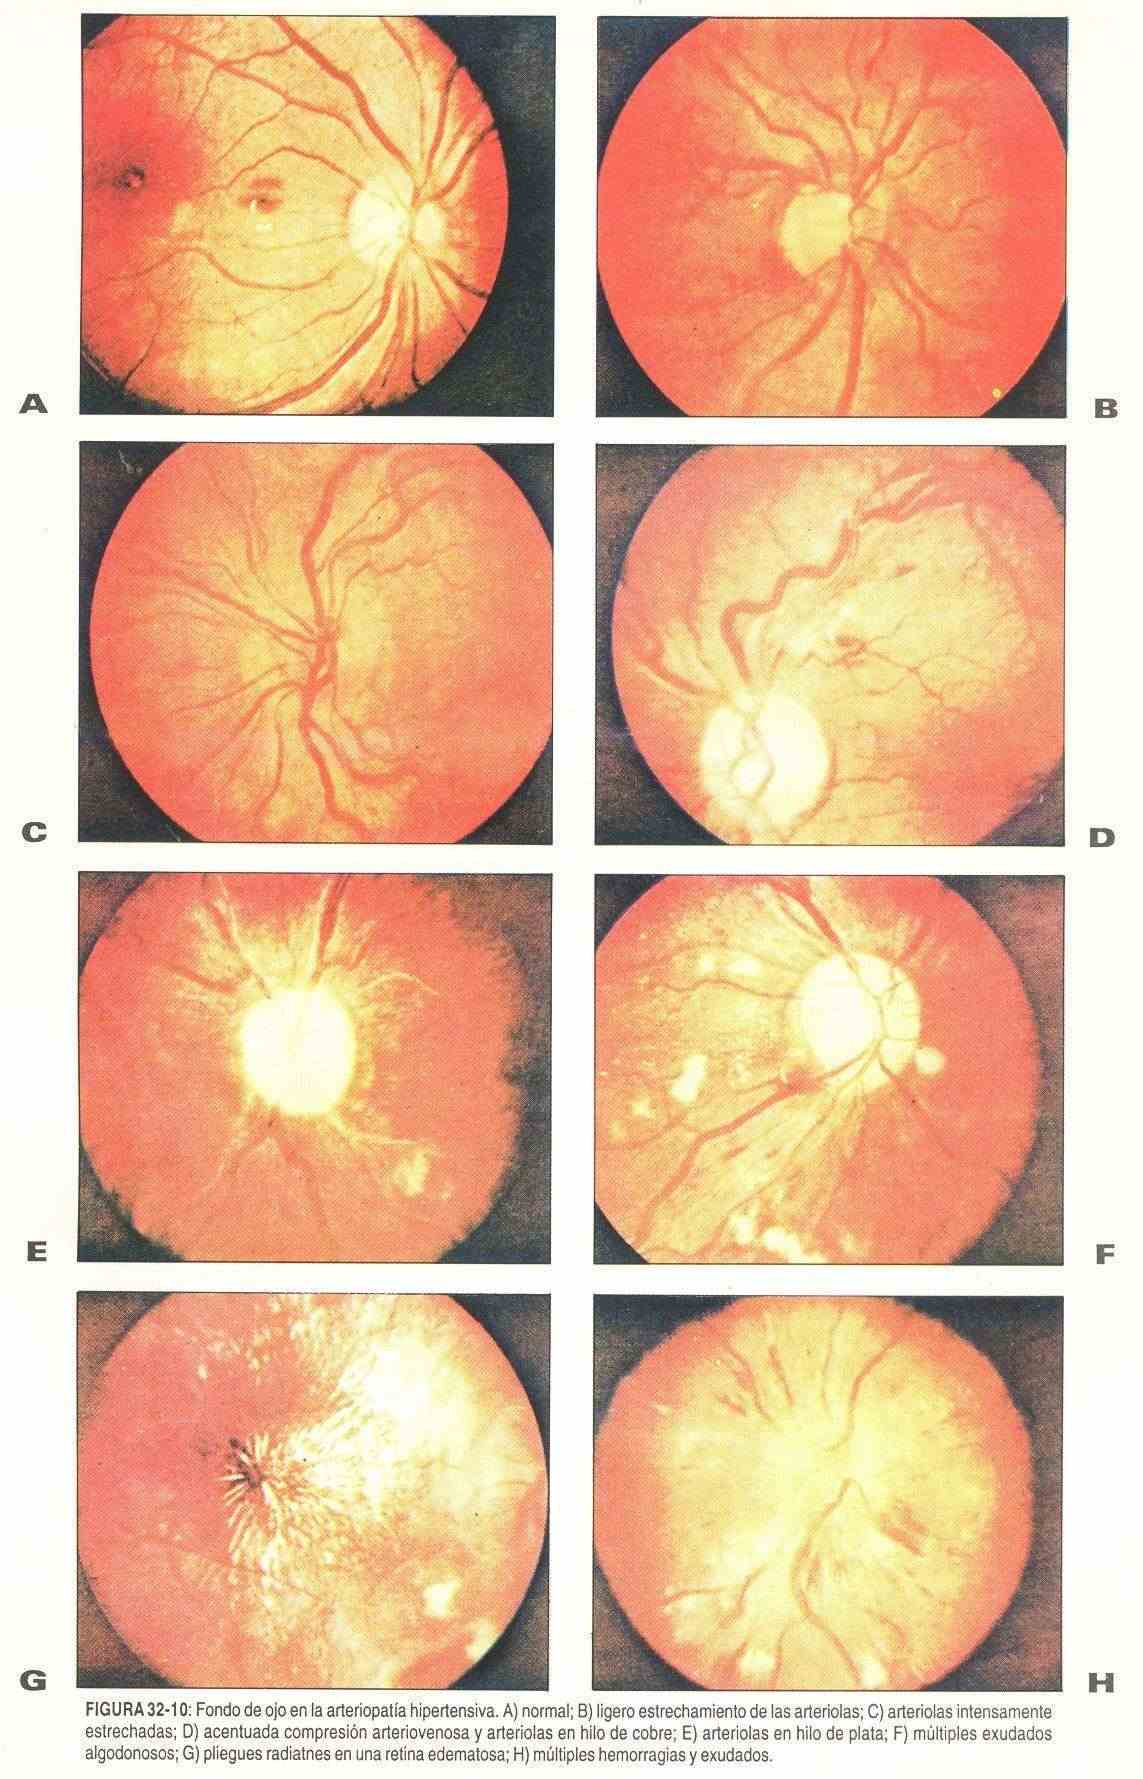

Retinopatía hipertensiva, diabética y arteriosclerótica. Los niveles elevados de presión arterial pueden producir cambios a nivel de la retina y de las arteriolas retinianas que se ponen de manifiesto en la observación oftalmoscópica (figura 32-10). El primer cambio que ocurre es el espasmo de los vasos con disminución del calibre de las arteriolas.

En pacientes jóvenes, con toxemia gravídica y con glomerulonefritis aguda, la elasticidad de los vasos permite que el proceso sea autolimitado, de modo que, cuando el nivel de la presión arterial vuelve a su normalidad, estos cambios desaparecen.

Cuando las cifras de presión se mantienen en forma sostenida, como en la hipertensión benigna, aparecen cambios más importantes. Estos incluye: tortuosidad de los vasos, compresión arteriovenosa o cruces arteriovenosos, con producción de las llamadas arterias en hilo de cobre y en hilo de plata.

En el paciente con hipertensión maligna aparecen los exudados algodonosos, las hemorragias, sobre todo en llama, y el edema de papila.